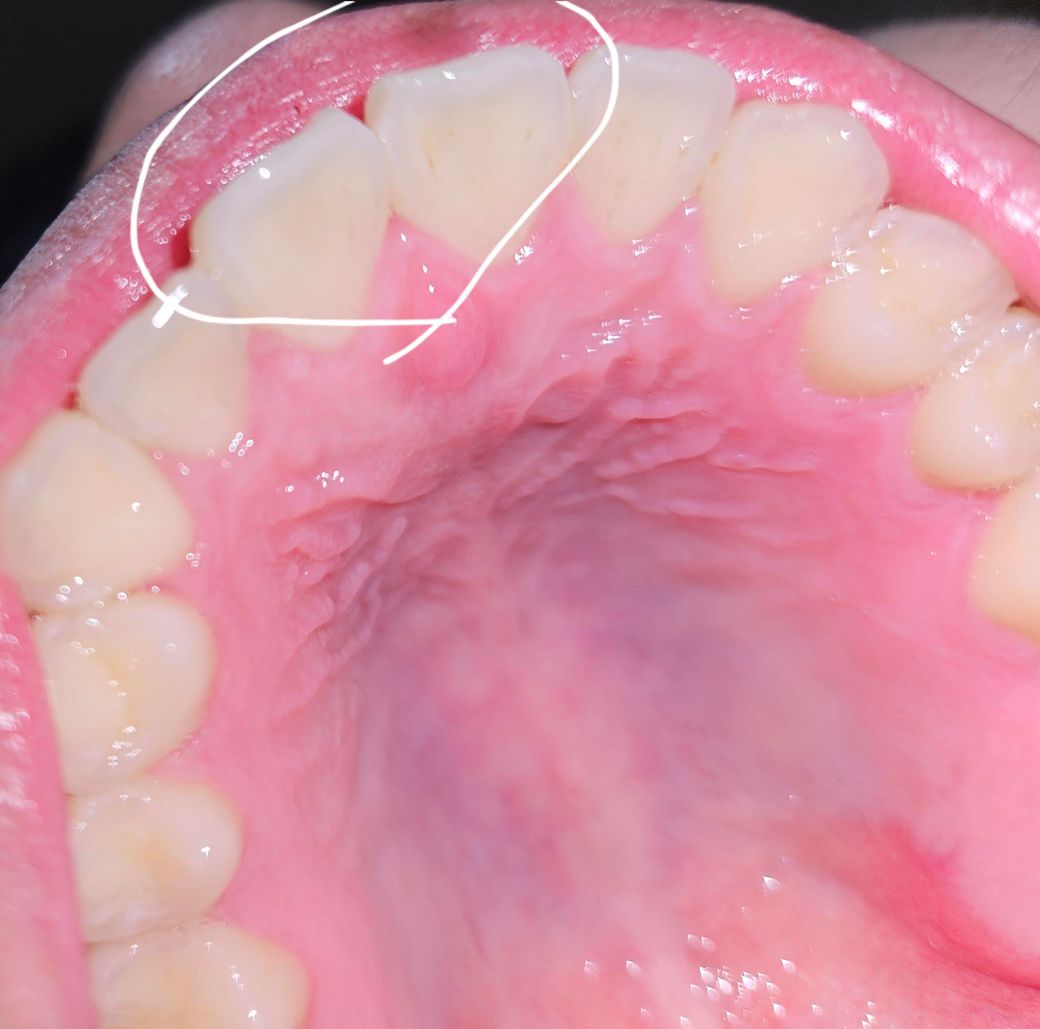

이빨이 계속해서 혀가 쓸리는거 같은데 혹시 이유가 뭘까여?

이빨에 계속해서 쓸려서 인지 혀 끝이 상처는 없지만 매일같이 아프다 나은게 2주째 입니다. 명확한 원인이 없다보니 치과가서 갈아주거나 다듬어 달라기에도 어렵네여 치아 부정교합 갈았던 이후에 이런거 같은데 갈고 다듬는 작업도 했습니다. 왜이런걸까여?

• 1번 째 사진

사진으로 봐서는 잇몸, 입천장 염증이 있어 부어있습니다 일단 전체적으로 청소를 위해 스케일링 및 잇몸치료를 받으면 좋을 것 같습니다